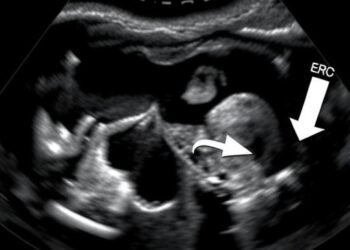

Linking Kids’ BMI to Liver Fat via Ultrasound

In a groundbreaking study set to reshape our understanding of pediatric health, a team of researchers led by Moeremans and ...